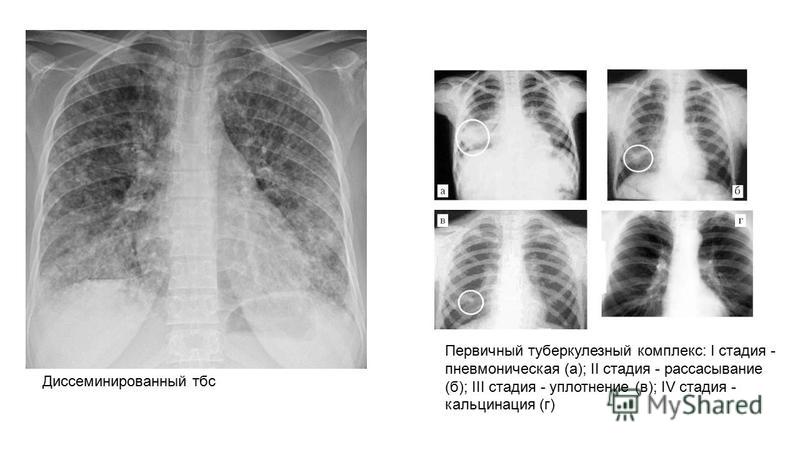

Ячеистая деформация легочного рисунка: медицинская визуализация